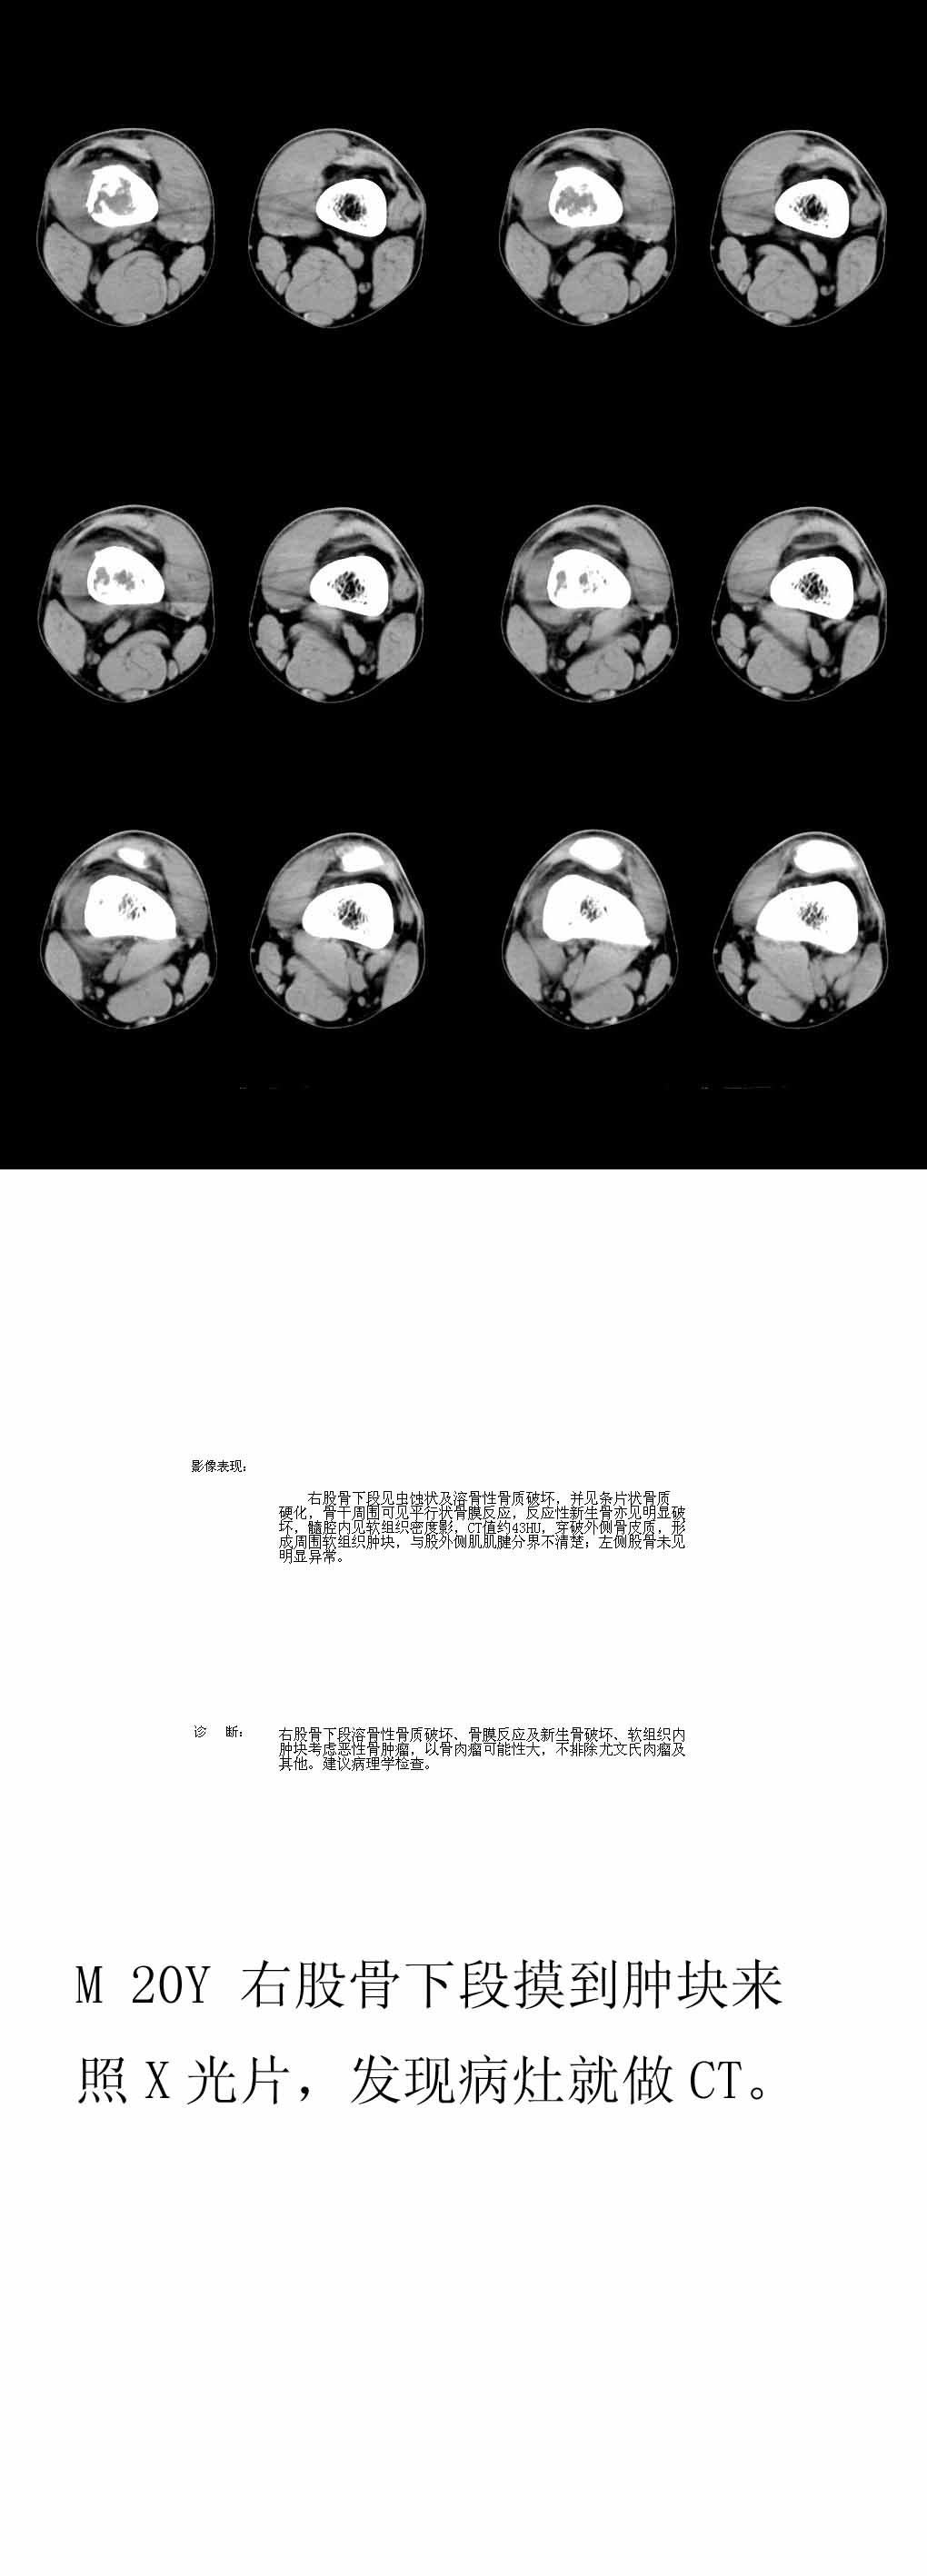

患者年龄、发病部位、ct表现:溶骨性骨质破坏、柳絮状肿瘤骨形成、骨膜增生、软组织肿块(虽然小)

都支持骨肉瘤的诊断,能够上传x线片就好了。

x线对骨膜反应及骨膜三角显示好,建议上传平片。同意骨肉瘤诊断(ct对骨质破坏,肿瘤骨及软组织肿块显示较好)。